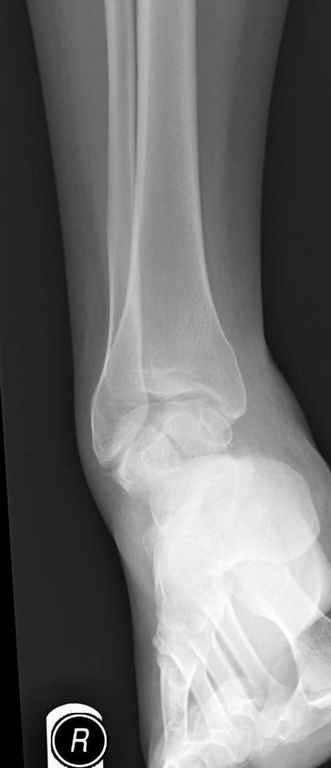

Уважаемые участники русского Ортофорума, поздравляю всех со всеми прошедшими праздниками: Новым годом, Рождеством, Hanukkah, Kwanzaa, желаю участникам всего наилучшего и здоровья.Повреждение таранной кости.Больной 81г автоавария, повреждение таранной кости, здесь снимки. Какие рекомендации?Djoldas Kuldjanov, MDDepartment of Orthopedic SurgerySt. Louis University Medical Center

Вдогонку по поводу перелома таранной кости, больная 81, не страдает диабетом, перелом закрытый, в первый же день поступления ограничились временным наружным фиксатором (как на снимке).

Планировалась открытая фиксация после спадения отека, но больная пожелала лечиться по месту жительству в другом штате..